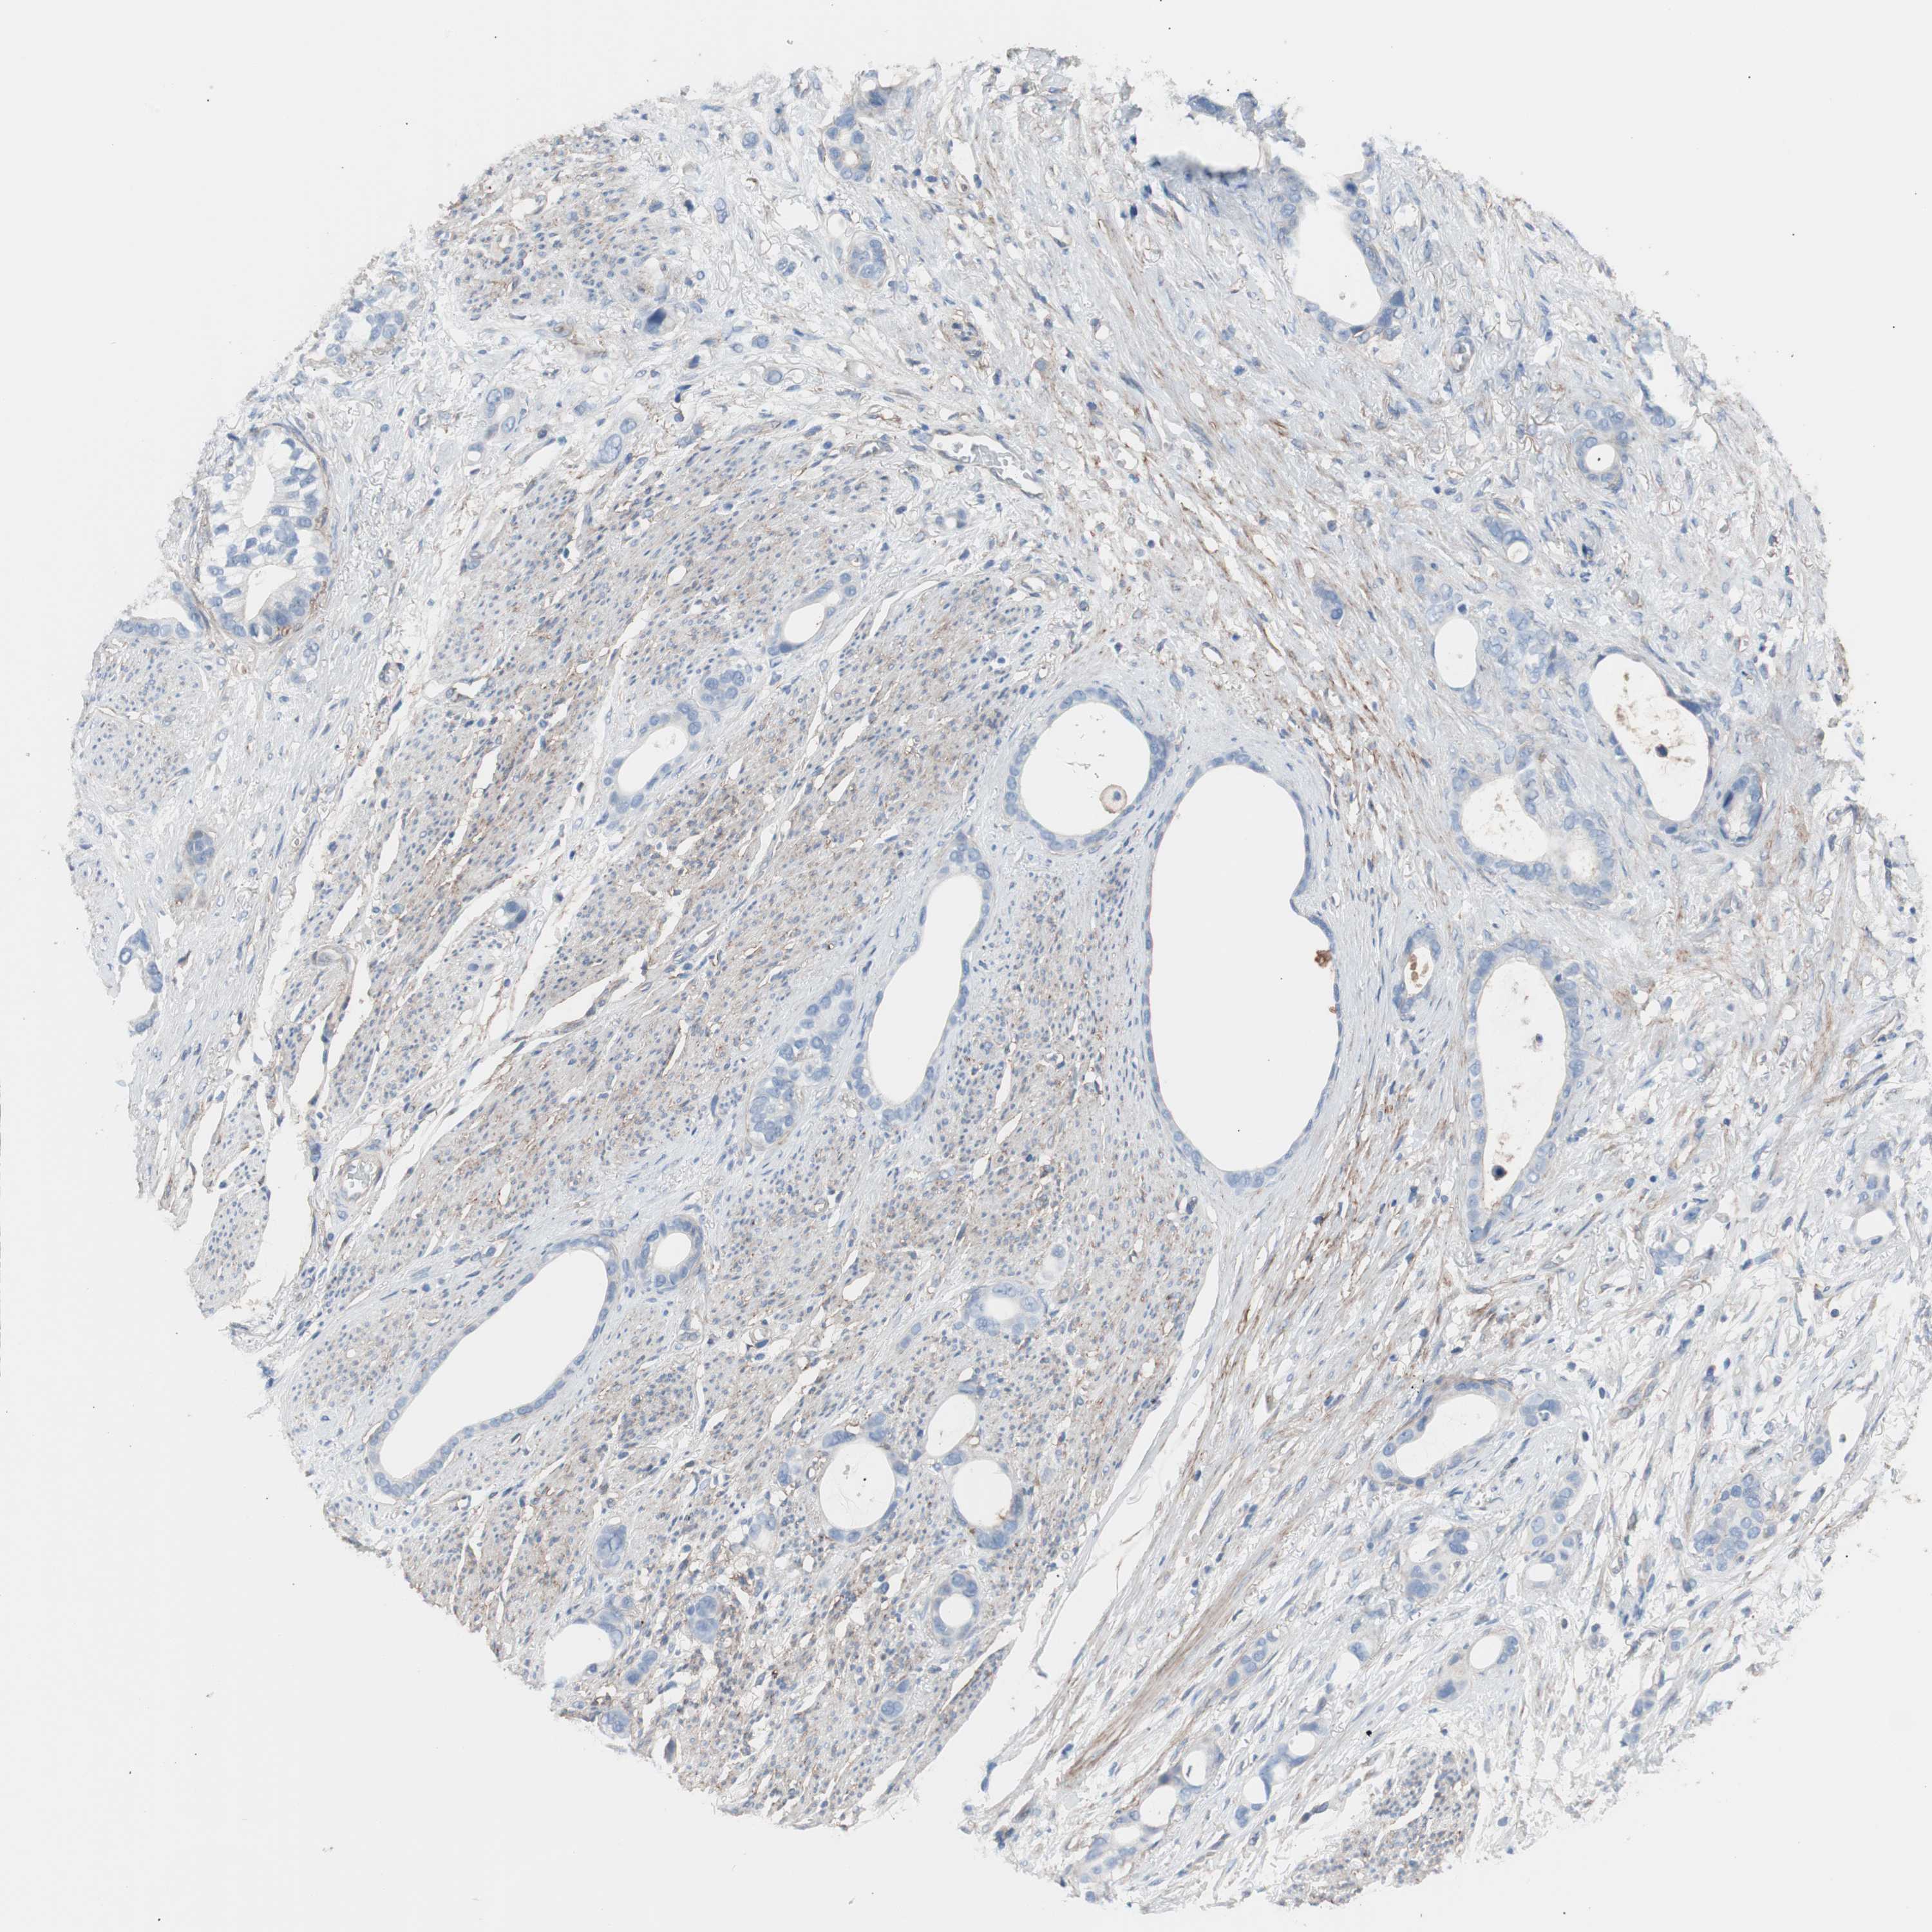

STOMACH CANCER - Protein expressioni

A mouse-over function shows sample information and annotation data. Click on an image to view it in a full screen mode. Samples can be filtered based on level of antibody staining by selecting one or several of the following categories: high, medium, low and not detected. The assay and annotation is described here.

Note that samples used for immunohistochemistry by the Human Protein Atlas do not correspond to samples in the TCGA dataset.

Antibody stainingi

Antibody staining in the annotated cell types in the current human tissue is reported as not detected, low, medium, or high, based on conventional immunohistochemistry profiling in selected tissues. This score is based on the combination of the staining intensity and fraction of stained cells.

Each image is clickable and will lead to virtual microscopy that enables deeper exploration of all samples and also displays staining intensity scores, fraction scores and subcellular localization as well as patient and tissue information for each sample.

Antibody HPA007234

Staining

High

Medium

Low

Not detected

Intensity

Strong

Moderate

Weak

Negative

Quantity

>75%

75%-25%

<25%

None

Location

Nuclear

Cytoplasmic/membranous

Cytoplasmic/membranous,nuclear

Adenocarcinoma, NOS